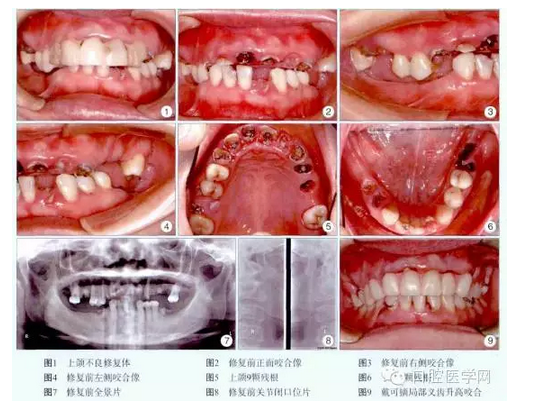

檢查:上前牙樹脂固定修復,松動。11、12、13、16、21、22、23、24、25、32、36、44、45殘根,叩痛(+),1度松動。26、31、37、46、47缺失,牙槽嵴較豐滿。14、15、17、27、33、34、35、41、42、43齲齒,叩痛(-),松動(-)。正中牙合位無牙合接觸,咬合垂直距離降低,息止牙合間隙6mm,張口度正常,無顳下頜關節(jié)彈響及觸痛,牙石I度,齦緣紅腫(圖1~6)。全景片示所有殘根根尖有透光區(qū),多數(shù)牙牙槽骨水平吸收約根長的1/4~1/3,可利用牙槽骨高度:16為12.5mm,24為14.9mm,26為11.0mm(圖7)。關節(jié)片未見明顯異常(圖8)。

診斷:①上頜不良修復體,②上下牙列缺損,③慢性牙周炎,④14、15、17、27、33、34、35、41、42、43齲齒,⑤11、12、13、16、21、22、23、24、25、32、36、44、45殘根。治療過程:術前拍全景片,關節(jié)片,取研究模,照數(shù)碼像,簽署知情同意書。潔牙,拔除11、16、22、24、25、36、44、45殘根。14、15、17、27、33、34、35、41、42、43用FiltekZ350納米樹脂(3M公司,美國)充填。膠托可摘局部義齒升高咬合4mm,重新建立新的頜位關系(圖9)。